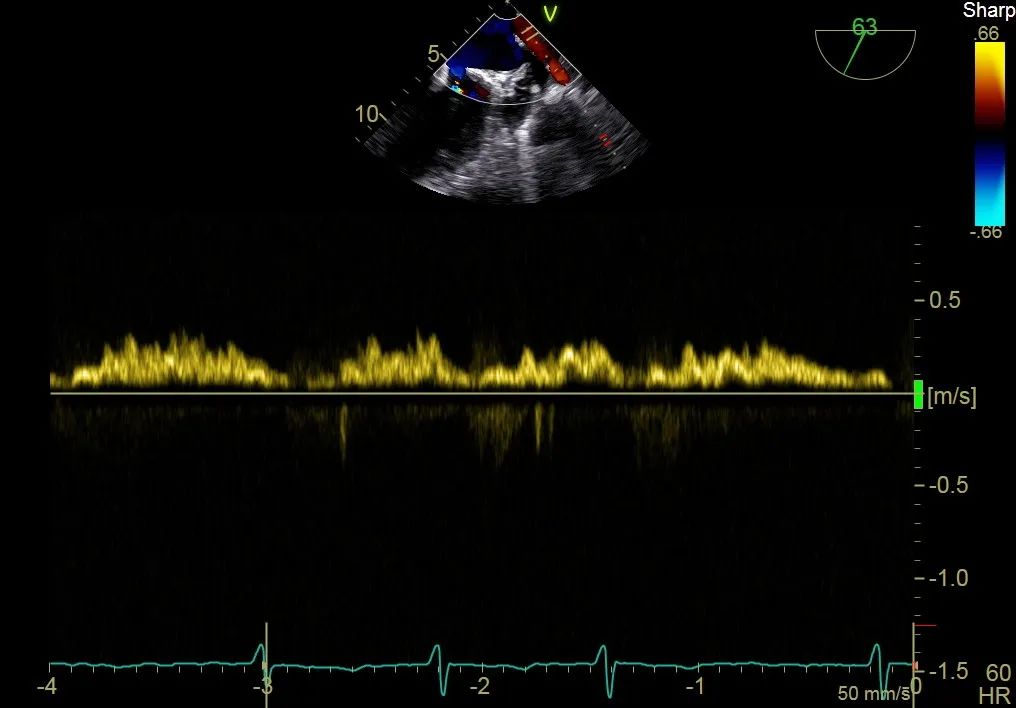

二尖瓣在收缩期变成双孔状,反流有效减小

再次反复测试第二枚二尖瓣钳夹的稳定性,超声复查提示二尖瓣反流明显改善,平均跨瓣压差4 mmHg